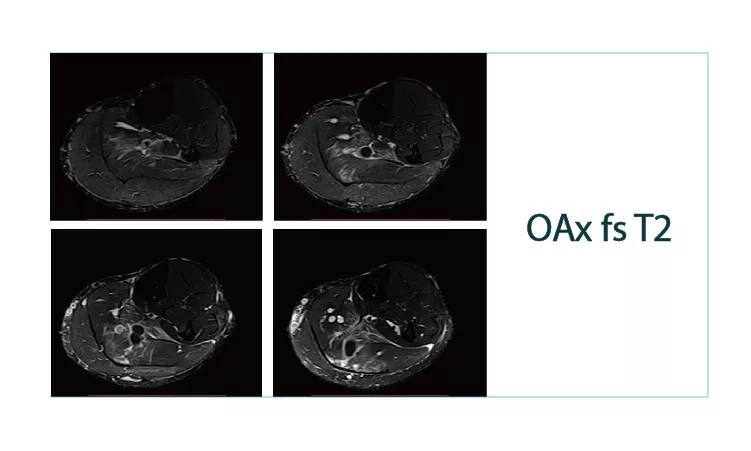

【朗润影像档案】磁共振影像病例分享(编号20180615)